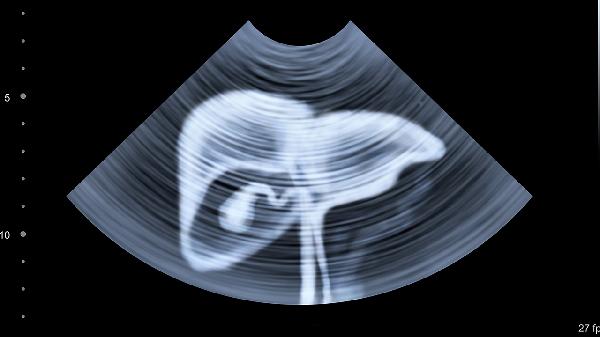

憋尿状态下充盈的膀胱能推开肠道,使子宫、卵巢、前列腺等盆腔器官充分暴露,尤其适用于经腹妇科超声和前列腺检查。不憋尿时膀胱未膨胀,肠道气体可能遮挡目标器官,仅适用于经阴道超声、经直肠超声或肾脏等非盆腔器官检查。

膀胱充盈后形成天然透声窗,超声波穿透性增强,可减少伪影干扰,提高分辨率。未憋尿时盆腔结构可能因肠气干扰出现图像模糊,微小病变检出率降低约30%,但经腔内超声探头因距离靶器官更近,不受此限制。